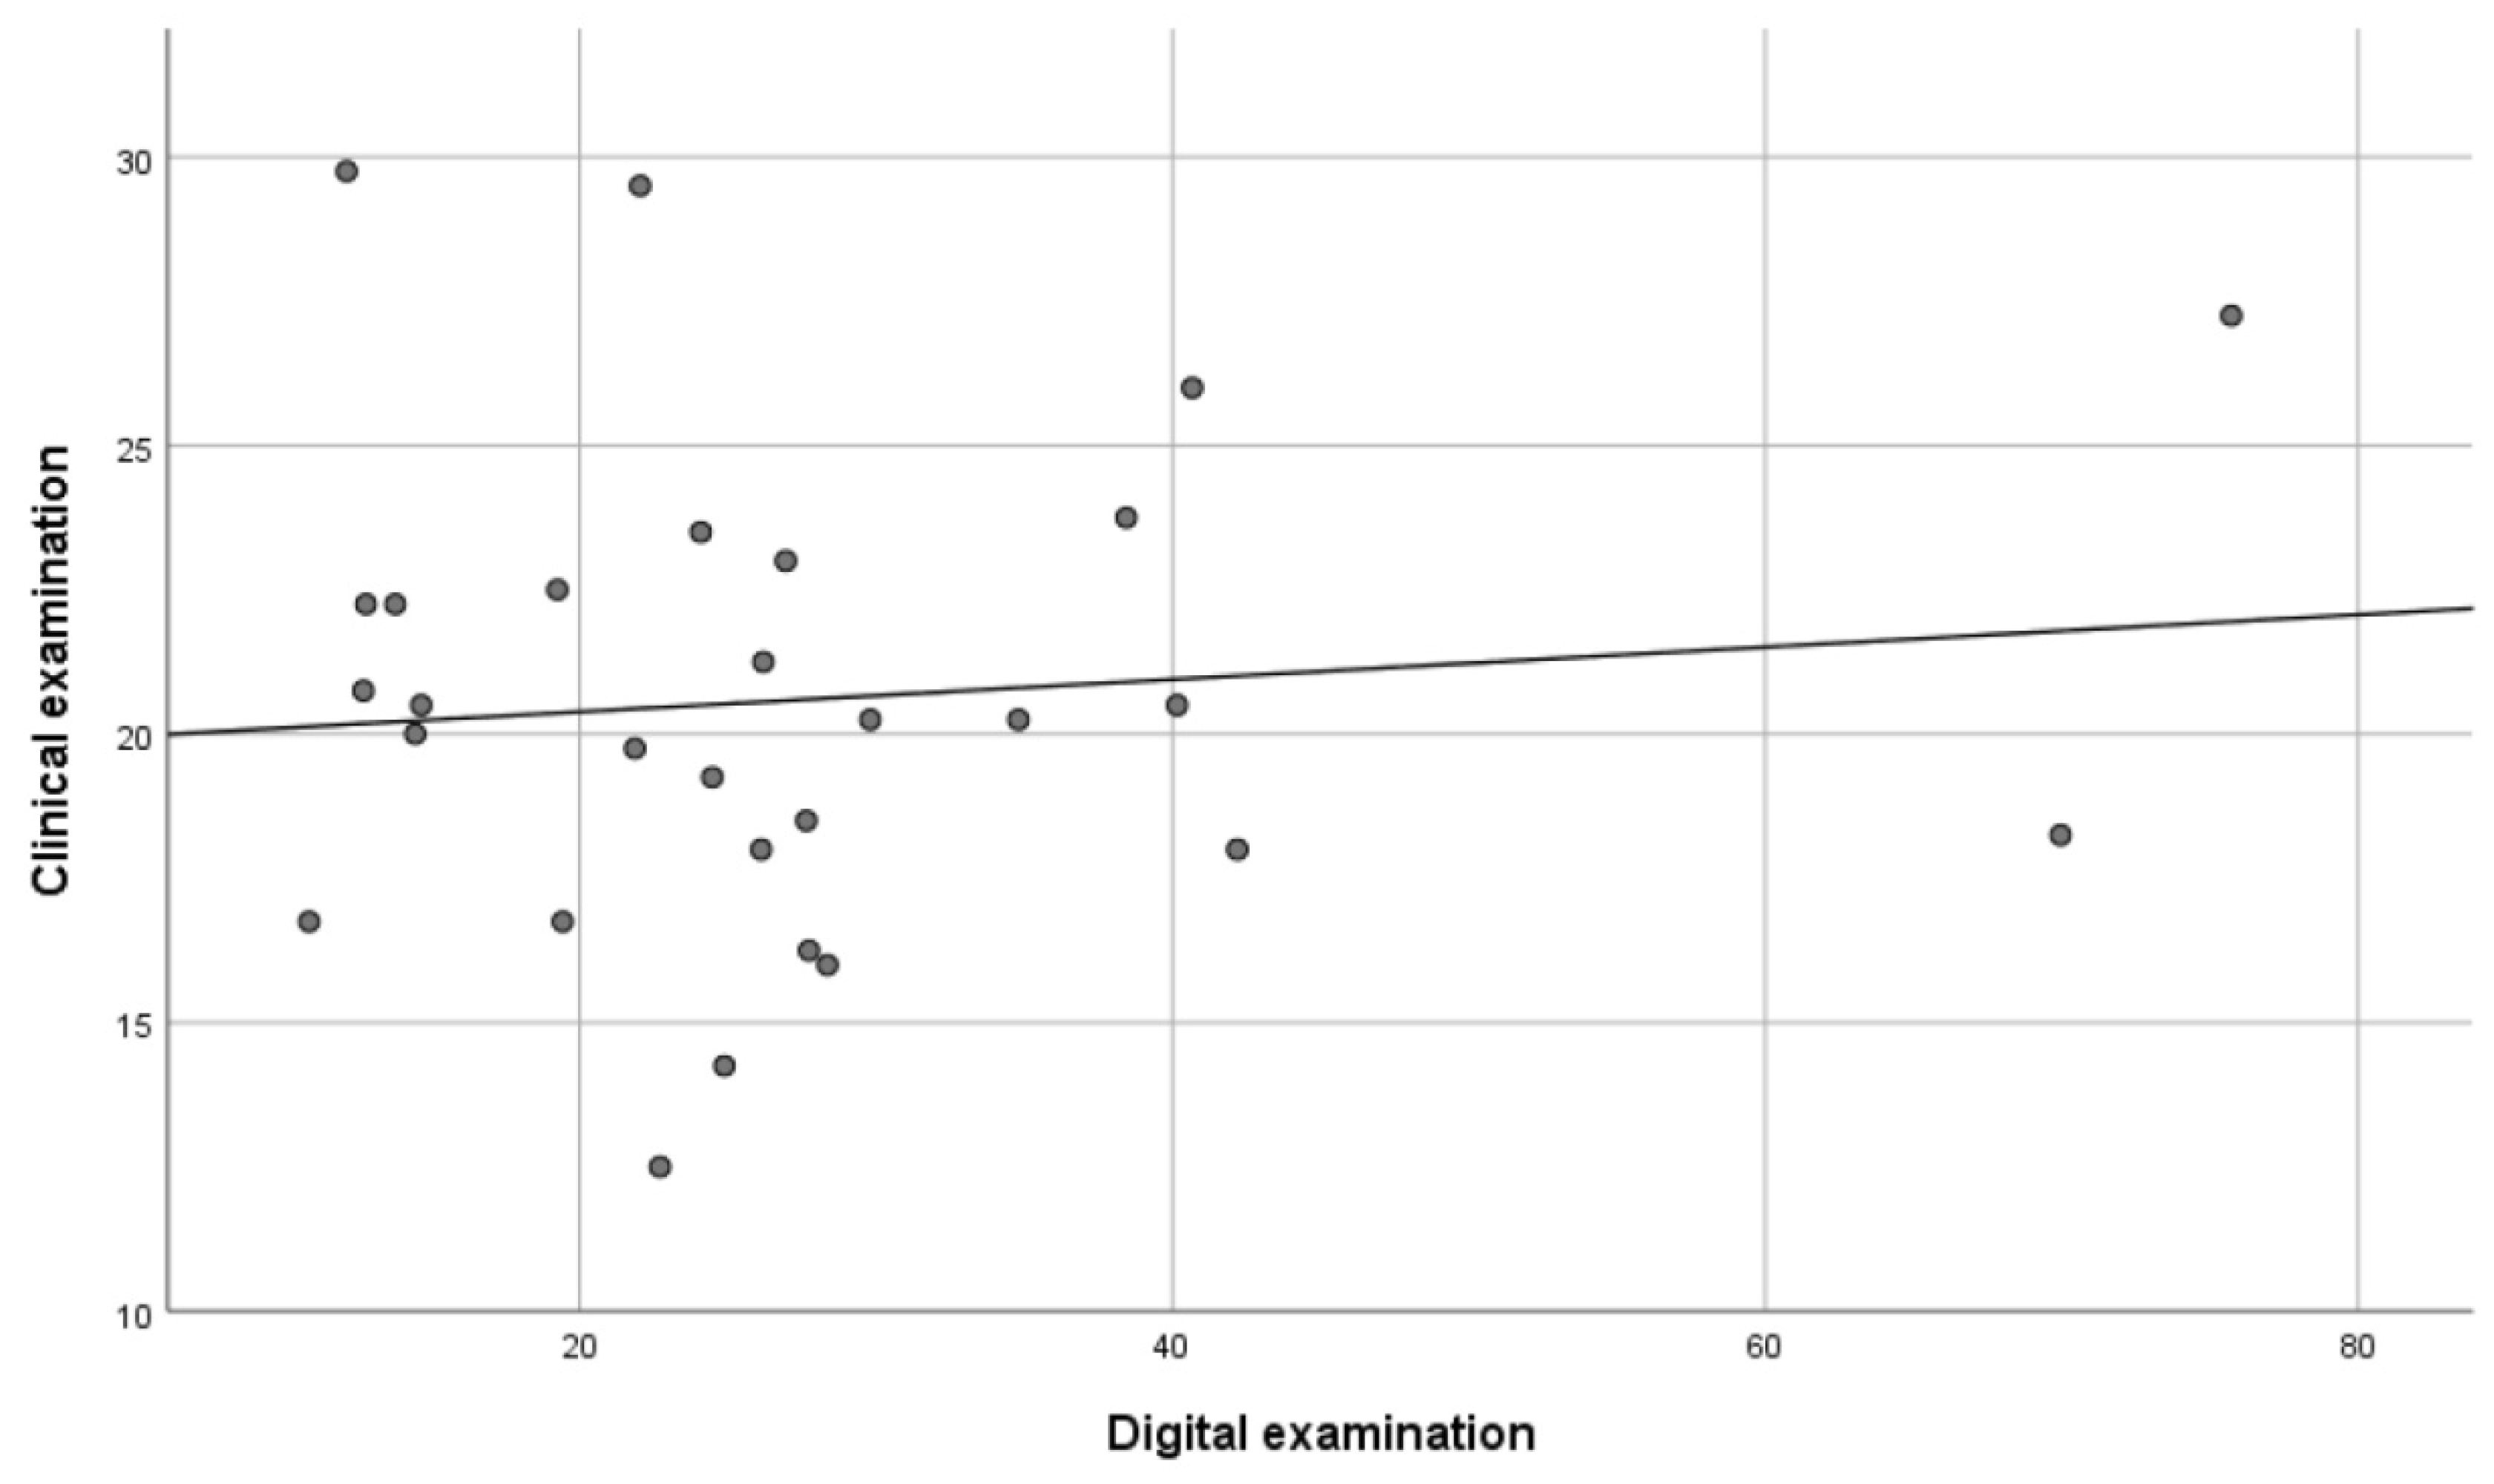

- a clinical examination with counting of the total number of occlusal contacts (CE method);

- a digital examination with the measurement of the total occlusal contact area in millimeters (DE method).